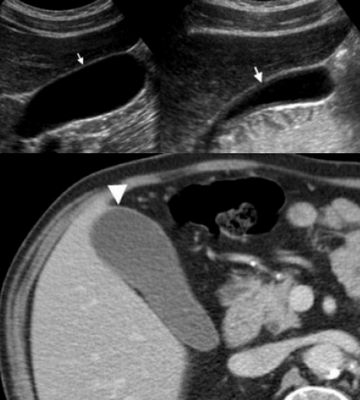

Сверху: УЗИ желчного пузыря стенка норма в виде «карандаша». Справа УЗИ картина псевдо-утолщения стенки желчного пузыря.

На КТ желчный пузырь в норме визуализируется, как образование с плотностью присущей мягким тканям. Указано стрелкой.

Утолщение стенки желчного пузыря — это частая диагностическая находка. Утолщением является размер стенки более 3 мм. При УЗИ утолщенная стенка имеет слоистый внешний вид, а на КТ выявляется гиподенсный слой, что соответствует субсерозному отеку.

Слева — УЗИ — желчного пузыря у 59 летней женщины с острым холециститом. Субсерозный отек так, как гипоэхогенное утолщение между гиперэхогенными слоями (мышечным и слизистым). Справа — КТ брюшной полости с контрастным усилением. Также визуализируется субсерозный отек так, как наружный слой гиподенсный.